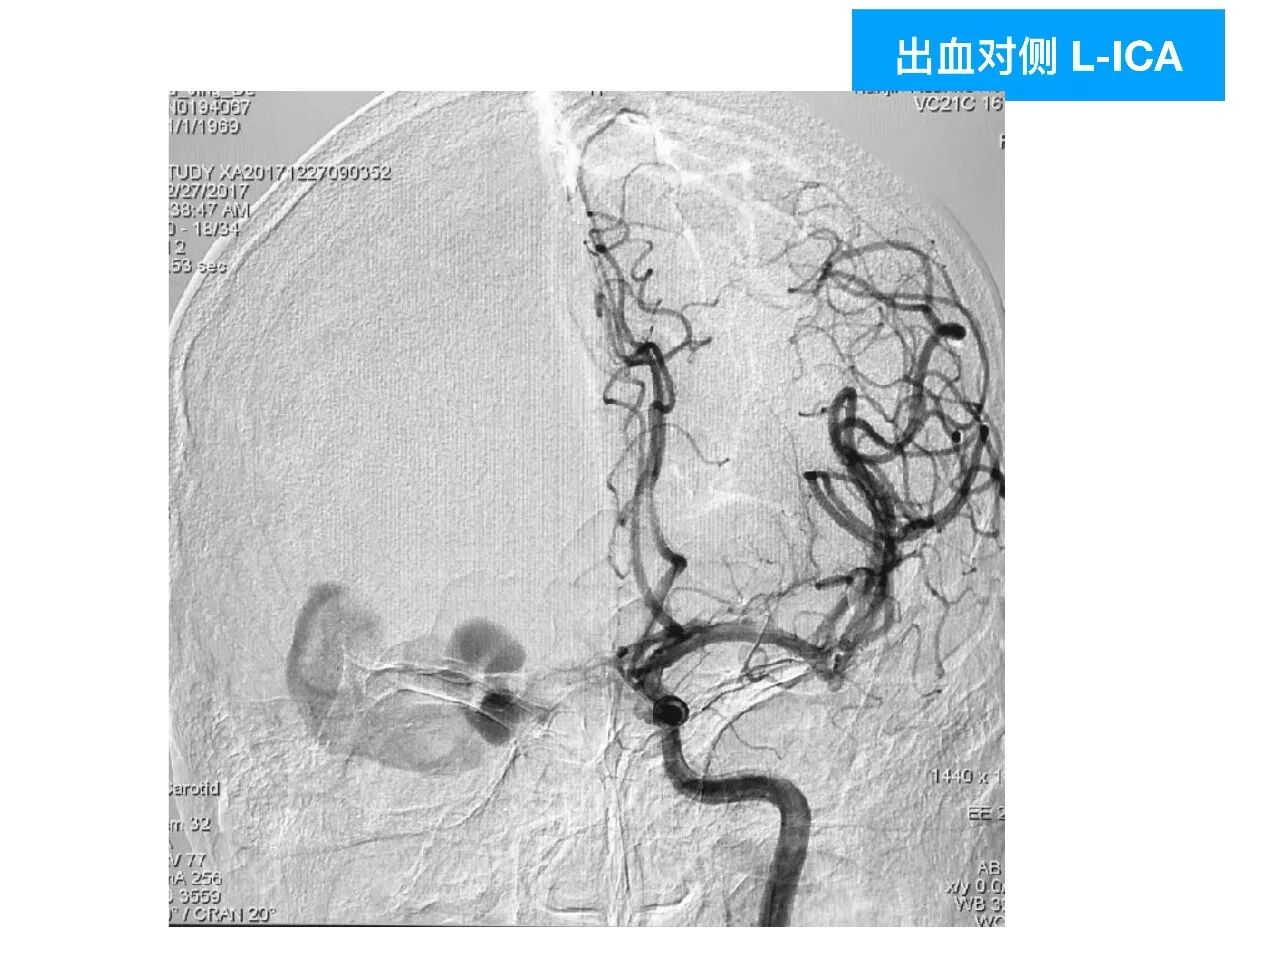

今天为大家分享的是《颅脑创伤-神经重症病例周刊》第四十九期,由天津市环湖医院神经外科五病区主任佟小光教授团队带来的:DAVF出血、脑疝急诊手术一例,欢迎阅读。

(1)DAVF引起如此严重的脑出血很少见,容易与普通脑出血混淆;

(2)DAVF即使术前很严重,及时闭塞DAVF,清除血肿,常常有好的预后;此例患者术前双侧瞳孔散大,术后回复超乎常规;

(3)对于此类DAVF,主要是蝶顶窦与海绵窦之间的逆流;扩大的中颅底入路,先闭塞引流入海绵窦的颈外动脉颌内动脉分支;然后将一侧海绵窦所有的漏口夹闭,切断所有的脑静脉与海绵窦逆流;

(4)虽然没有处理颈内动脉-海绵窦漏,在漏口闭塞后,所有的漏几乎都消失了。